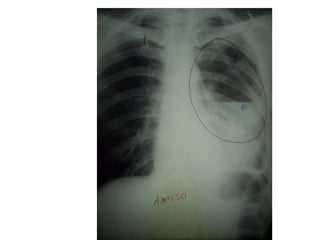

Caverna por TBC

Quiste Hidatidico

Bula pulmonar